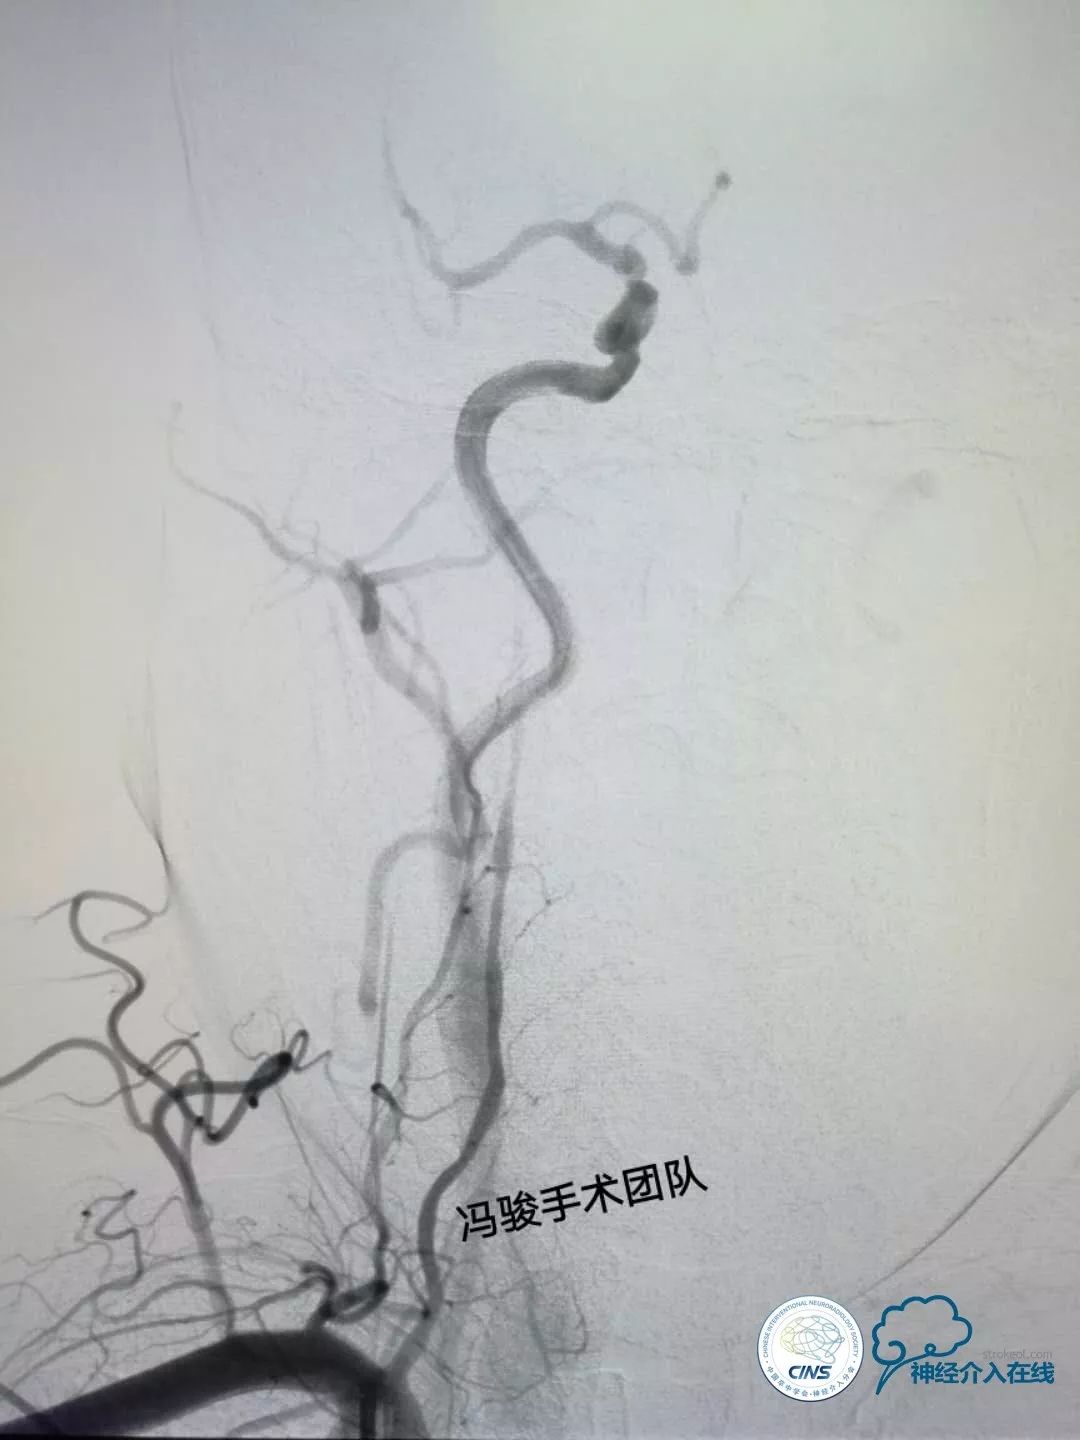

彩超示:右椎动脉先天未发育,左椎动脉远端血流受阻。DSA造影如下:

DSA显示,患者右椎动脉发育不良,V2段远端闭塞,仅存的左椎动脉串联病变,V1段迂曲,V4段99%狭窄(并局部溃疡),且病变处发出左小脑后下动脉(PICA),PICA亦99%狭窄,可谓“命悬一线”!